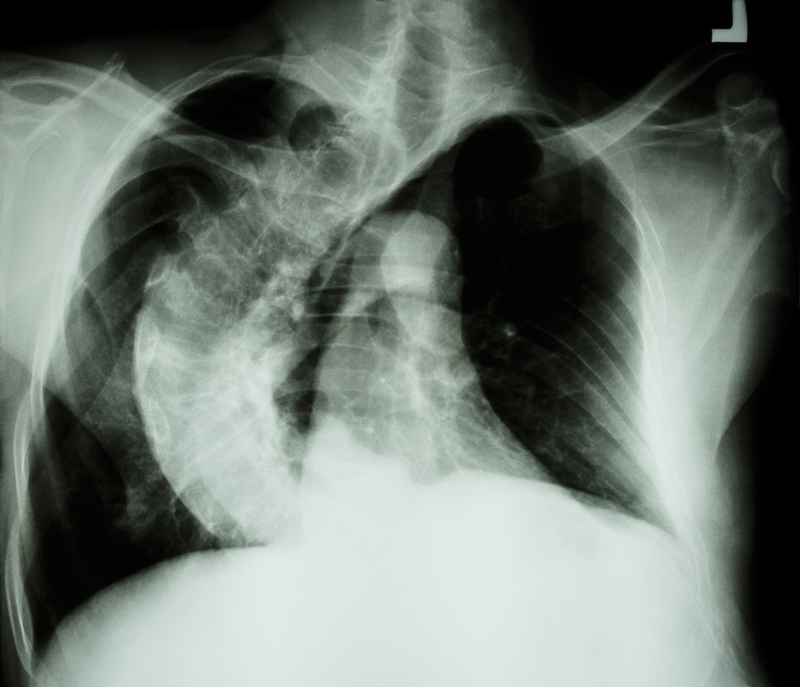

"Posterior Spinal Scoliosis Correction and Instrumented fusion T1-L4 with costoplasty T3-8 was successfully performed. Post-surgery the patient was breathing well and within two days, he was able to walk independently. He was discharged five days post-surgery and the X-rays done revealed that the scoliosis curve was corrected to 50-degree and the kyphosis was corrected to 60-degree. A month and a half after his surgery, the patient's chest constriction has eased, and his quality of life has improved significantly," said Dr Vidyadhara while speaking on the procedure performed to treat the patient.

Disclaimer: Image used is for illustrative purposes only and does not represent a true or accurate depiction of the news report.